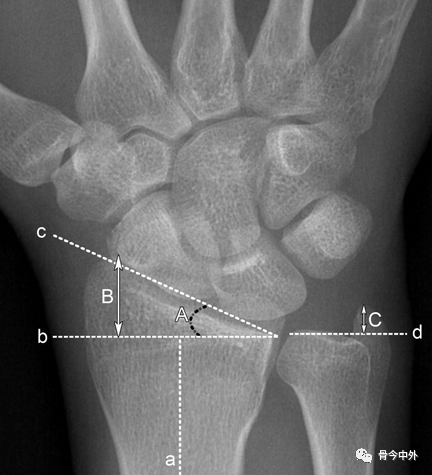

图4 a.桡骨纵轴线;b.桡骨纵轴线垂线;c.桡骨远端关节面切线;d.尺骨远端关节面水平线。A.桡骨内倾角;B.桡骨茎突长度;C.尺骨茎突长度 。

A.正常为15~35˚ 。若此角度改变,提示桡骨远端骨折或腕关节脱位。

B.正常为8~18mm,且桡骨茎突较尺骨茎突低1~1.5cm。若此长度改变,提示桡骨远端骨折。C.正常为2~8mm。若此长度改变,提示尺骨茎突骨折或尺骨茎突过长(尺骨茎突撞击综合症)